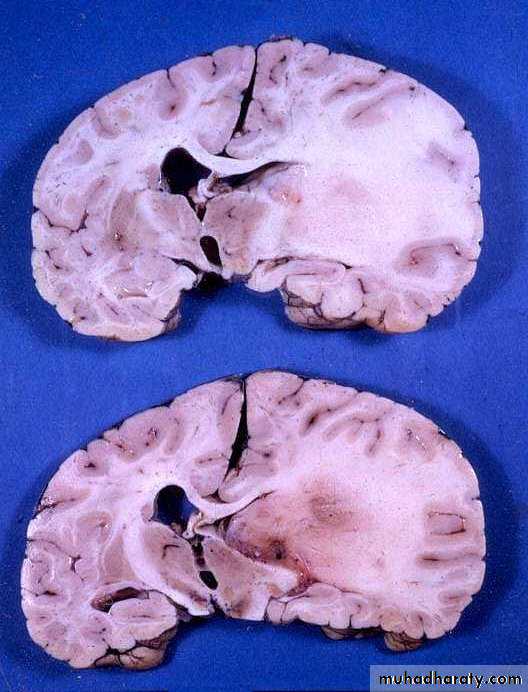

Gliomas

They are derived from cells of glial origin.

• They are the commonest of primary CNS neoplasms.

• They form 50% of adult intracranial tumours.

• They are of four types: astrocytoma, oligodendroglioma, ependymoma and choroid plexus papilloma. The most common of which is astrocytoma.

• Survival is closely associated with grading.

• Treatment involves surgery and radiotherapy and/or chemotherapy.